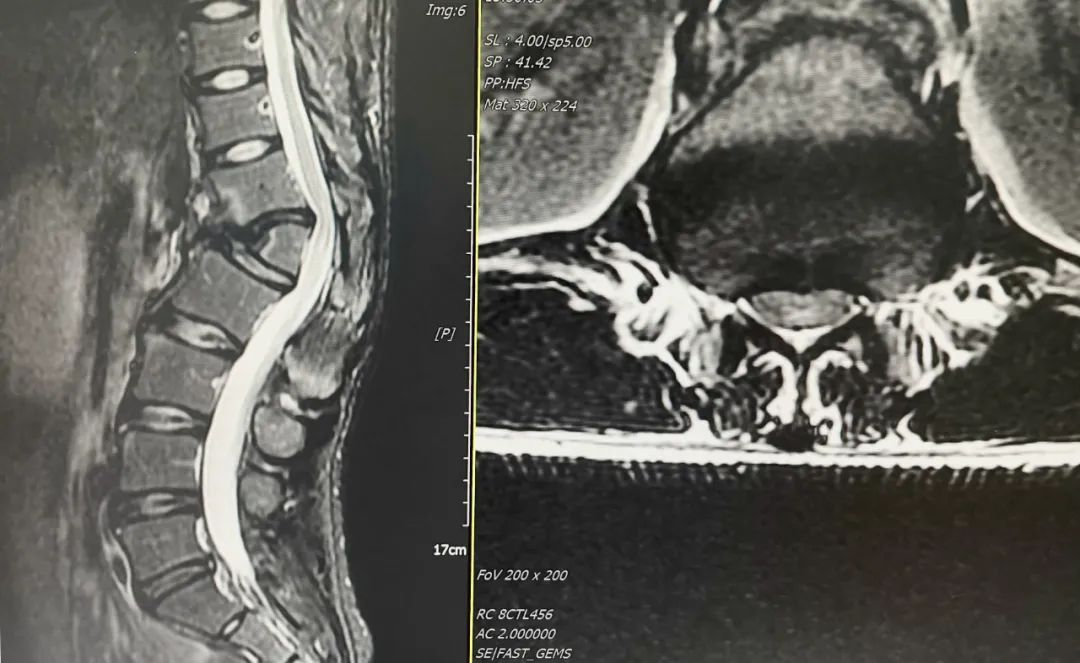

▲MRI平扫示:脊髓圆锥受压缺血受损